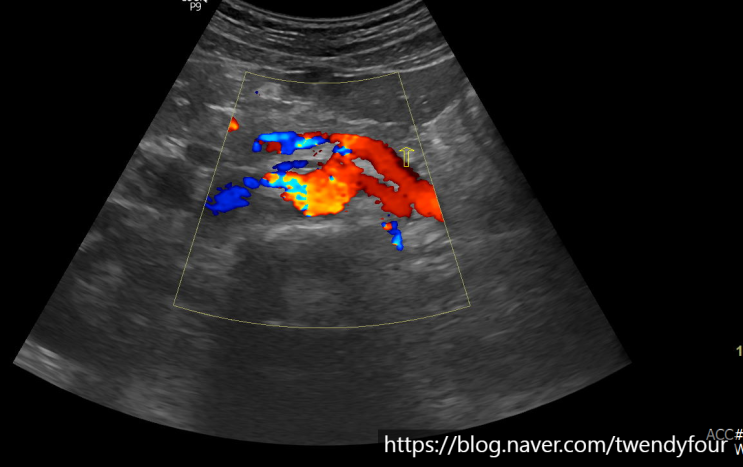

전립선비대증(BPH)의 초음파 검사 안녕하세요, 영원한 스물넷 트웬디포입니다. 오늘은 초음파로 간단히 ...